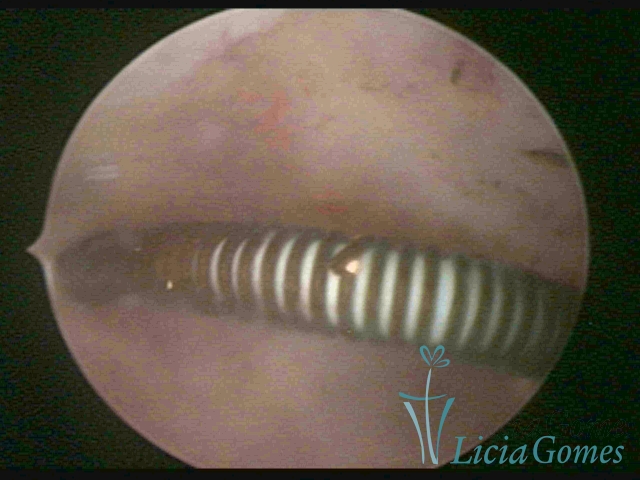

Cervical canal with IUD string